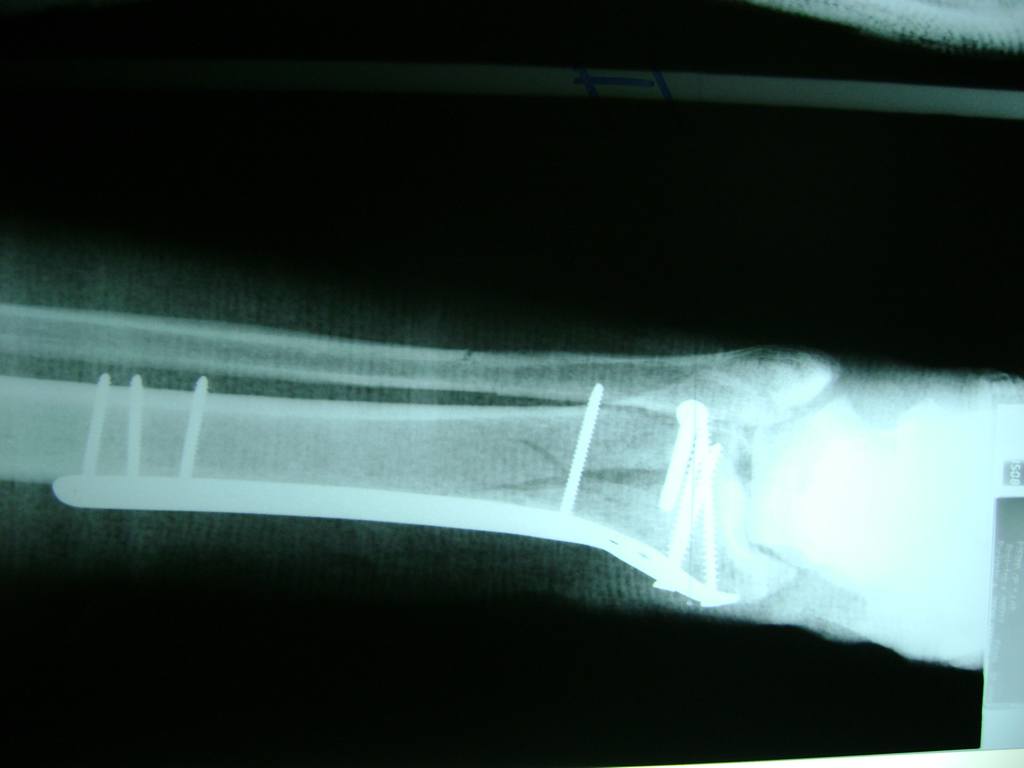

Cirugías de Peroné y Tibia

Cuando se necesita cirugía, es probable que esta implique el uso de clavijas de metal, tornillos o placas para sostener los huesos en su lugar mientras la fractura se consolida. Los elementos de soporte pueden ser temporales o permanentes.